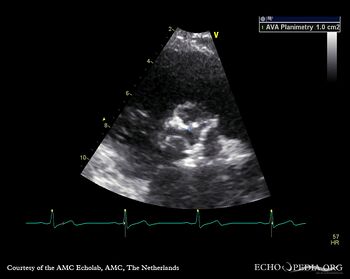

PSAX: planimetry of aortic valve area